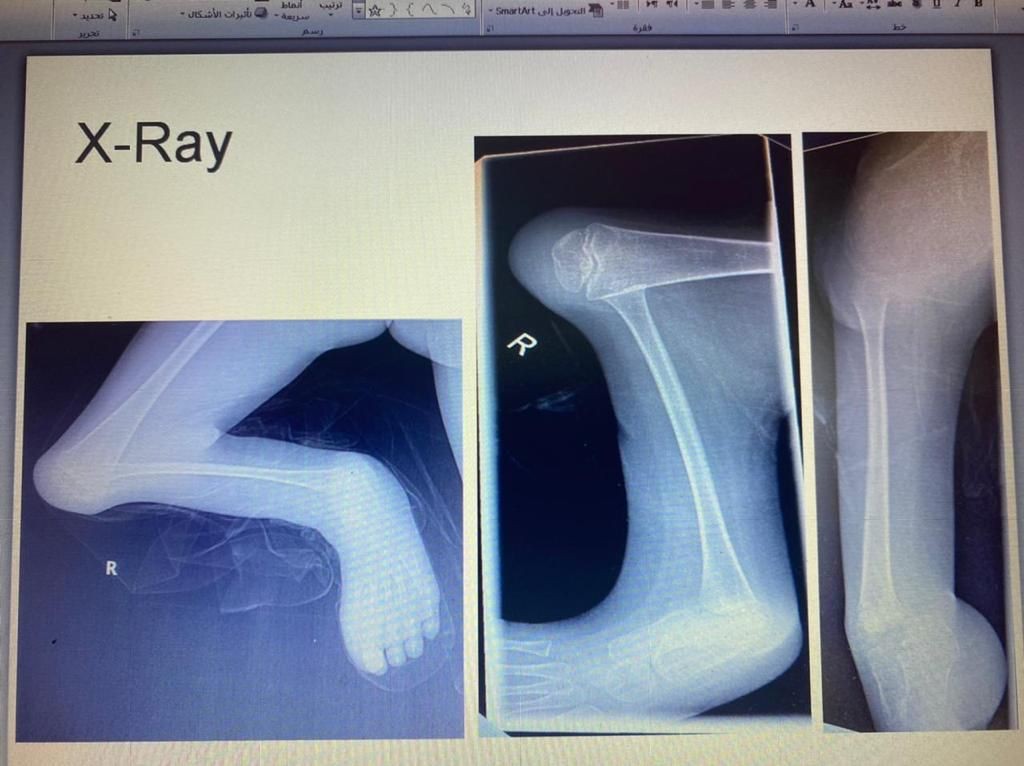

نجح الفريق الطبي في قسم جراحة العظام بمستشفى الملك فهد العام بجدة بقيادة الدكتور عبدالهادي العمودي من إجراء عملية جراحية لطفل بعمر 8 اعوام في ساقه اليمنى تحديداً بعظمة القصبة الرئيسية وإيجاد عظمة شظية ثانوية بالساق اليمنى.

وبعد عمل الفحوصات الطبية اتضح أن الطفل يعاني من تشوه خلقي لفقدانه عظمة القصبة بالساق اليمنى وتم قيام الفريق الطبي بإجراء عملية جراحية تكميلية لعظمة الشظية بالساق لتعويض القصر في العظمة، وتمكن الأطباء بعملية توفير عظمة الشظية من عظمة الفخذ باستخدام جهاز الاليزروف وتم تعديل القدم تحت عظمة القصبة بالشظية وإدراج القدم تحت عظمة الشظية.

ثم بفضل الجهود المتواصله من قبل الفريق الطبي المتمكن تكللت العملية الجراحيه بنجاح ولله الحمد وعودة الساق إلى شكلها الطبيعي بعد أن كانت العظمة مفقودة.